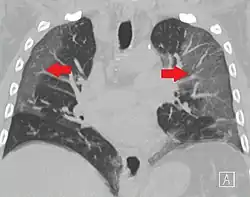

High-resolution CT image showing ground-glass opacities in the periphery of both lungs in a patient with COVID-19 (red arrows). The adjacent normal lung tissue with lower attenuation appears as darker areas.

CT image in patient with COVID-19 showing bilateral ground-glass opacities at the periphery of both lungs.

Ground-glass opacity is among the most common imaging findings in patients with confirmed COVID-19.[16][17] One systematic review found that among patients with COVID-19 and abnormal lung findings on CT, greater than 80% had GGOs, with greater than 50% having mixed GGOs and consolidation.[16] GGOs with mixed consolidation has most often been found in elderly populations.[18] Several studies have described a pattern among initial, intermediate, and hospital discharge imaging findings in the disease course of COVID-19. Most commonly, initial CT imaging reveals bilateral GGOs at the periphery of the lungs. During initial stages, this is most often found in the lower lobes, although involvement of the upper lobes and right middle lobe has also been reported early in the disease course.[16][18] This is in contrast to the two similar coronaviruses, SARS and MERS, which more commonly involve only one lung on initial imaging.[19][20] As the COVID-19 infection progresses, GGOs typically become more diffuse and often progress to consolidation.[11][18] This is sometimes accompanied by the development of a crazy paving pattern and interlobular septal thickening.[18] In many cases the most severe pulmonary CT abnormalities occurred within 2 weeks after symptoms began.[17] At this point, many individuals begin showing resolution of consolidation and GGOs as symptoms improve. However, some patients have worsening symptoms and imaging findings, with further increase in septal thickening, GGOs, and consolidation. These patients may develop lung "white-out" with progression to acute respiratory distress syndrome (ARDS) requiring treatment escalation.[17][21]

Preliminary reports have shown many patients have residual GGOs at time of discharge from the hospital. Due to the novelty of COVID-19, large studies investigating the long-term pulmonary CT changes have yet to be completed. However, long-term pulmonary changes have been seen in patients after recovery from SARS and MERS, suggesting the possibility of similar long-term complications in patients who have recovered from acute COVID-19 infection.[22]